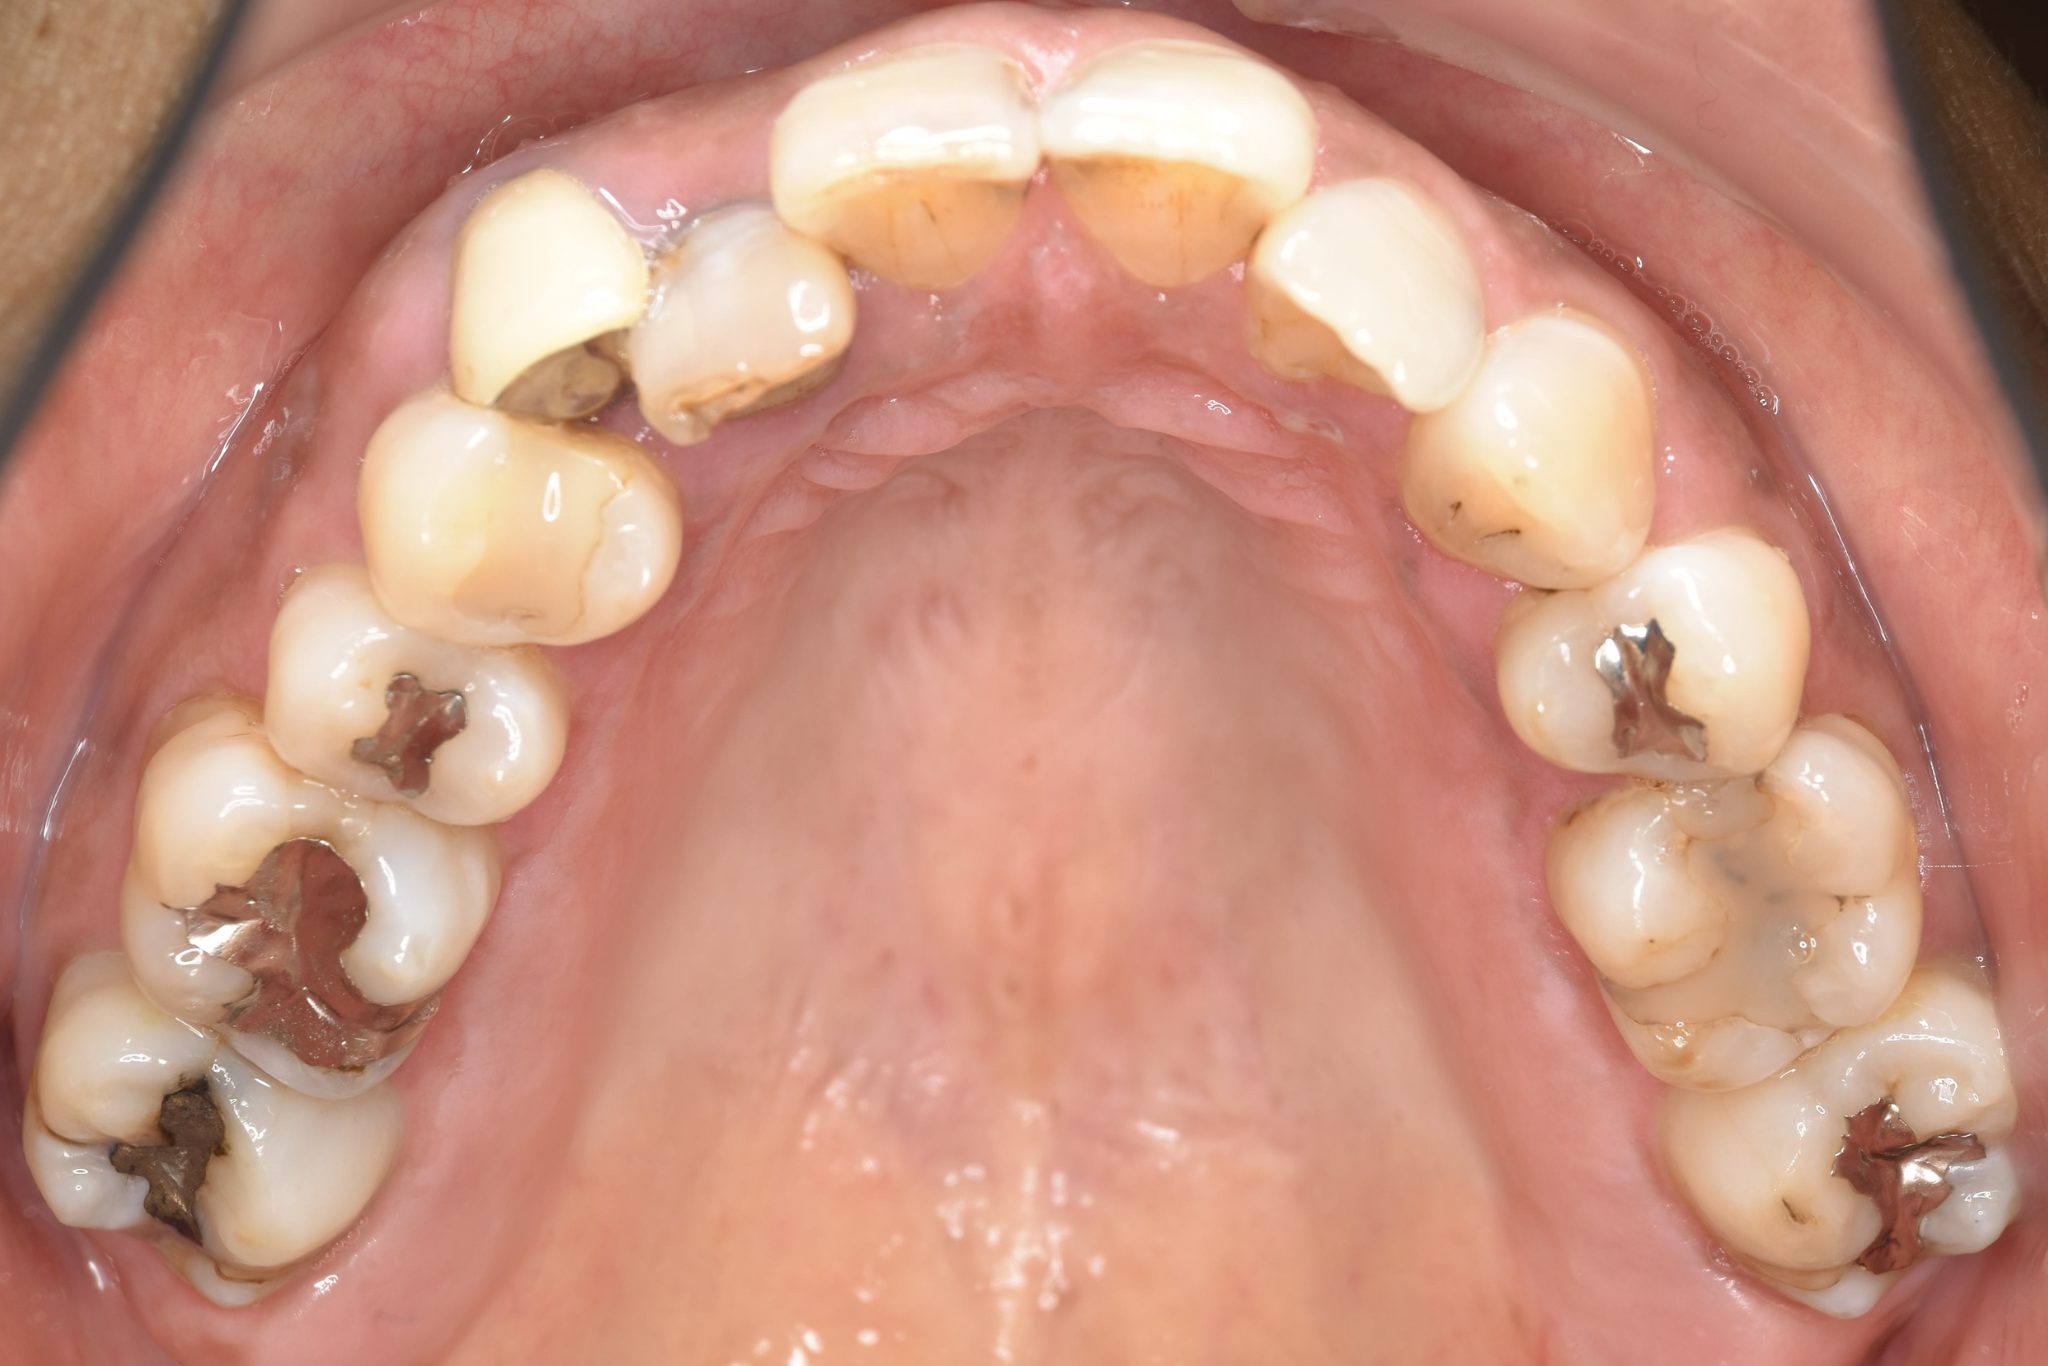

ビフォー

ワイヤー矯正治療|症例_588

主訴 かみ合わせ ※抜歯あり

施術内容 MSEと下顎リンガルアーチを用いて上下顎骨を拡大した。

その後下顎前歯を1本抜歯してマルチブラケット装置を用いて

歯牙を配列し良好な咬合を獲得した。側貌は改善した。